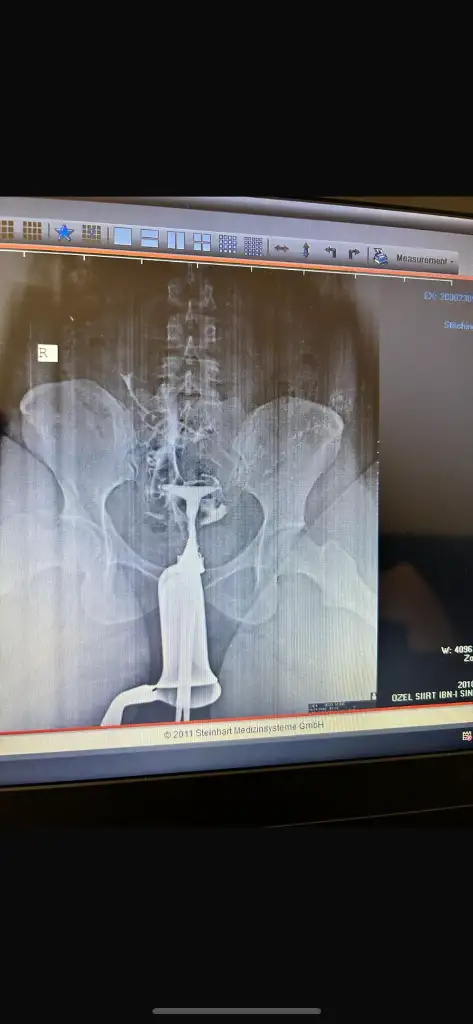

Dogustan sanırım kürtajla ilgisi yoktur canım Oyüzden histeroskopi diye bir ameliyat var zaten şekil olarak t olduğu için t rahim deniyor bazıları y rahim bazıları kalp benim bariz t idi baksana